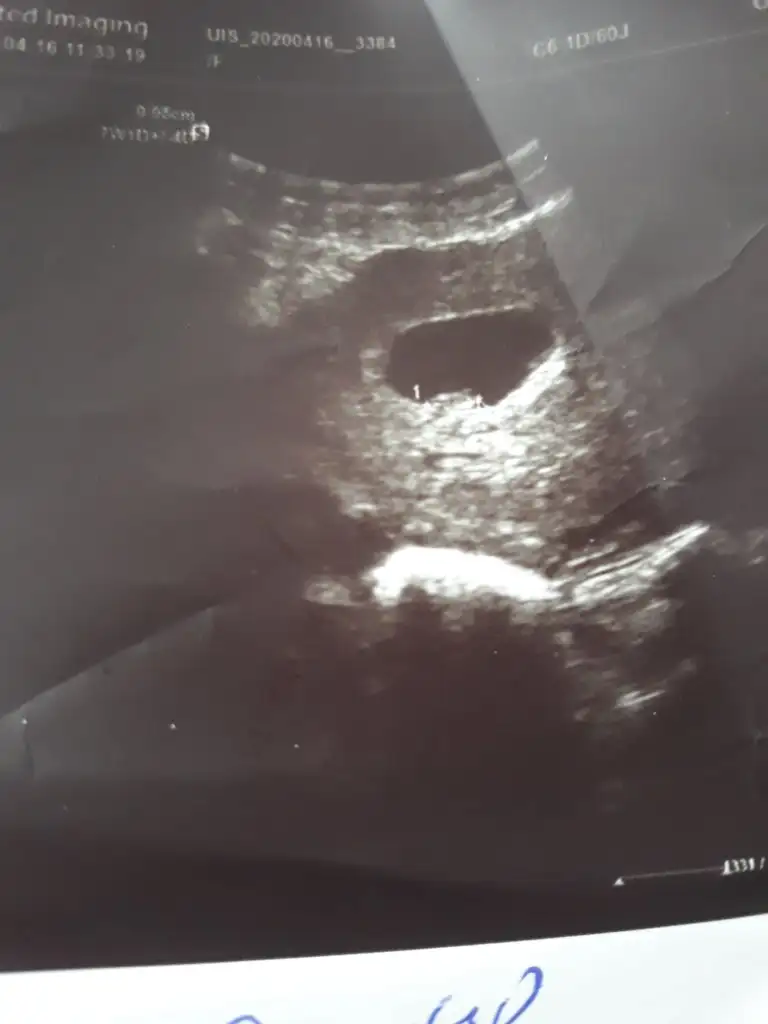

Buna göre kızKarindan usg 7+4kizlar yorum yapacak olan varsa cok mutlu olurum

Bundan sonra gidemeyecgm sanirim cinsiyet vakti 14 15 .haftalar giderim nasil anladiniz kiz acabaBuna göre kızama siz 11 12 13 hafta nub için paylaşın

Çok tesekkur ederim zahmet olmasa buna da bakabilir misiniz kardesimin 8 haftalikBuna göre kızama siz 11 12 13 hafta nub için paylaşın